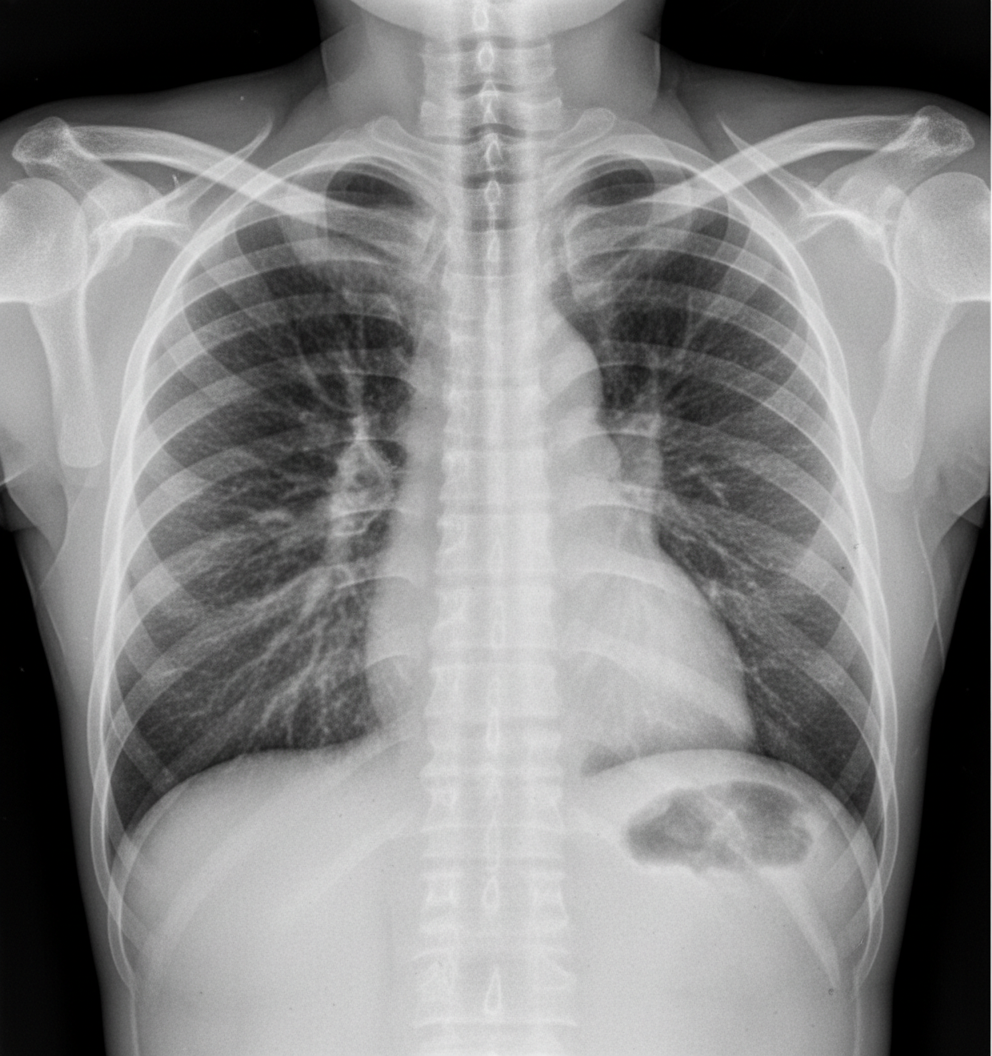

A patient presents with acute epigastric pain and an increase in serum lipase. Several days after stabilization, a chest X-ray shows bilateral diffuse infiltrates. What is the most common pathology explaining the chest X-ray findings?

Explanation: ***Non-cardiogenic pulmonary edema*** - The patient's presentation with **acute epigastric pain** and **elevated serum lipase** is consistent with **acute pancreatitis**, which is a known cause of **ARDS (acute respiratory distress syndrome)**. - The chest X-ray findings of **bilateral diffuse infiltrates** without signs of cardiomegaly or pleural effusions are characteristic of **non-cardiogenic pulmonary edema** caused by ARDS. - ARDS complicates approximately **10-20% of severe acute pancreatitis cases** and presents with hypoxemia and bilateral pulmonary infiltrates. *Increased PCWP* - **Increased pulmonary capillary wedge pressure (PCWP)** is characteristic of **cardiogenic pulmonary edema**, where a failing heart causes increased pressure in the lungs. - The X-ray findings and clinical context of pancreatitis suggest a **non-cardiac cause** for the pulmonary edema, and PCWP would be **normal or low in ARDS**. *Pulmonary thromboembolism* - **Pulmonary embolism (PE)** often presents with **dyspnea, pleuritic chest pain**, and sometimes **tachycardia** or **hemoptysis**. - Chest X-rays in PE are often **normal** or show subtle findings like **Westermark sign** or **Hampton's hump**, which are not seen here. - The **bilateral diffuse infiltrates** are not typical of PE. *Aspiration pneumonitis* - **Aspiration pneumonitis** typically occurs in patients with impaired consciousness or dysphagia and usually presents with infiltrates in **dependent lung segments**, often the right lower lobe. - While pancreatitis can lead to nausea and vomiting, the **diffuse and bilateral** nature of the infiltrates is less typical for a primary aspiration event. *Pleural effusion* - **Pleural effusions** are a common complication of acute pancreatitis (occurring in up to **20% of cases**), typically left-sided or bilateral. - However, the described chest X-ray findings of **bilateral diffuse infiltrates** represent **parenchymal disease**, not simply fluid in the pleural space. - Pleural effusions would appear as **blunting of costophrenic angles** or fluid layering, not diffuse infiltrates.